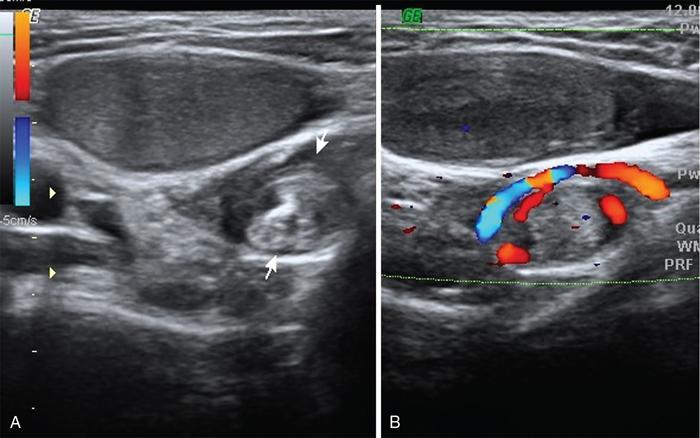

Intraabdominal testis is more prone for malignant transformation whereas canalicular testis for torsion (bulky heteroechoic testis, devoid of internal vascularity, with adjacent whirlpool sign or mass). In canalicular torsion testis the child usually presents with acute painful groin swelling (Figs. 11.8.7–11.8.8).

Fig. 11.8.7A 13-year-old male child (known case of palpable right UDT) presented with acute painful swelling right groin area. US and colour Doppler scan of inguinal region shows hypoechoic small-sized undescended right testis at superficial inguinal ring level with twisted spermatic cord in inguinal canal (whirlpool sign between arrows and vascular twist on colour Doppler), s/o torsion of undescended right testis.